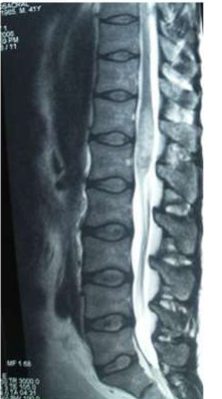

Images (4 & 5) MRI of Case No (6). Showing cauda equina expansion and hyperintense patches of in the cauda equine of both T1 and T2 weighted MRI.

Eight of the ten patients were diagnosed utilizing MRI which showed Dorsal 12 to Lumber 1 or 2 spinal cord swelling with hyper intense patches in T2 images , while the remaining two patient were diagnosed utilizing CT myelogram which showed Dorsal 12 to Lumber 1 or 2 spinal cord swelling.

Magnetic resonance imaging in spinal schistosomiasis usually shows swollen conus and epiconus beside areas of hyper-signal in T2 and heterogeneous contrast enhancement[12]. Multinodular intramedullary contrast enhancement of the distal cord allowed accurate preoperative MR imaging diagnosis of spinal schistosomiasis[12]. Cerebrospinal fluid (CSF) may show changes in spinal schistosomiasis. Characteristic features are mild to moderate pleocytosis, presence of eosinophils, slight to moderate protein increase, elevated gamma globulin concentration and a positive immune assay. These abnormalities are not always, accidentally schistosomal ovae may appear in the cerebrospinal fluid [13].